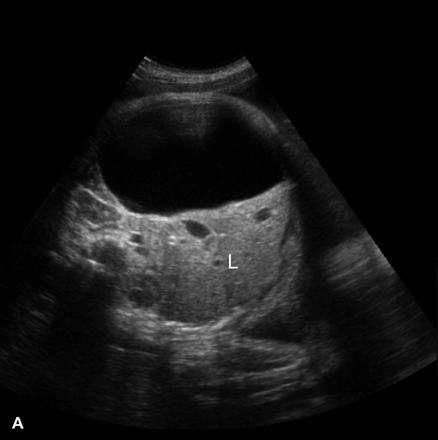

What is Cirrhosis?

A chronic degenerative disease in which there is parenchymal necrosis, regeneration and fibrous tissue resulting in disorganization of lobular architecture. Lobules are infiltrated with fat. Commonly caused by alcoholism.

What is the sonographic appearance of Cirrhosis?

Hepatomegaly

Increased echogenicity and attenuation

Size

decrease of right lobe

Size increase of left and caudate

lobe

Nodularity

Fibrosis

Hepatospenomegaly

Ascites

Portal

hypertension

Hepatoma tumors

caudate lobe may be spared

What are the presenting symptoms of Cirrhosis?

fatigue

bruises

jaundice

edema

dark urine

blood in stool

fever

Echogenic portal radicals

flatulence.

What are the lab values that would suggest Cirrhosis?

↑Alk Phos

↑Direct Bilirubin

↑AST

↑ALT

Leukopenia